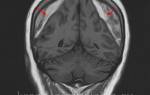

2 | Компьютерная и/или магнитно-резонансная томография головного мозга | по показаниям |

В острых случаях туберкулезного менингита мозг обычно бледен и извилины несколько уплощены. Экссудат покрывает мягкие мозговые оболочки в основании черепа и распространяется вдоль латеральной борозды. Милиарные бугорки видны в мягких мозговых оболочках. Наиболее явно они наблюдаются вдоль сосудов, в основном средней мозговой артерии. Микроскопически бугорки состоят из скопления круглых клеток, в основном мононуклеаров, часто в центре имеется казеоз. Гигантские клетки выявляются редко. В мозговом веществе отмечаются проявления воспалительных реакций, выражена токсическая дегенерация нервных клеток. При лечении антибиотиками базальный экссудат становится плотным и в больших артериях, проходящих через него, может развиться артериит, в результате чего возможно возникновение инфаркта мозга. Адгезии и спайки могут вызвать гидроцефалию либо обструкцию спинального субарахноидального пространства.